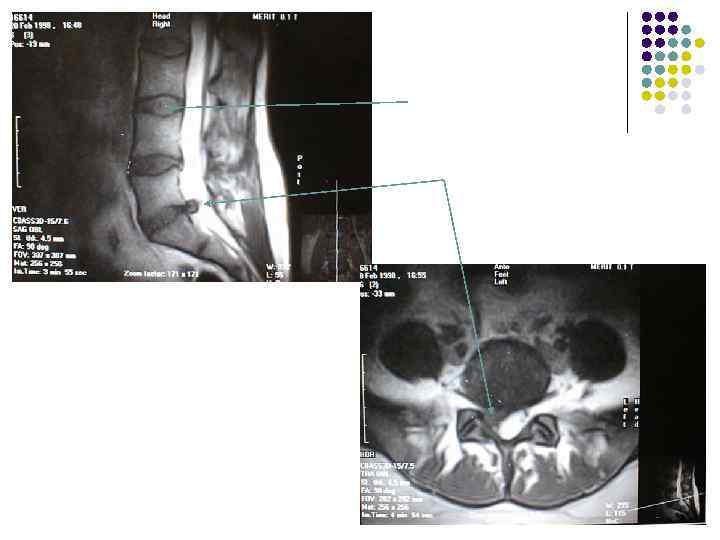

МРТ грыжа- дискография